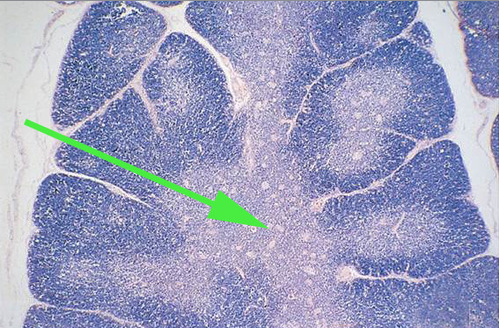

Areas of diffuse lymphatic tissue are found in the walls of the structures marked by the green arrows. They are called the///small intestine

The light area indicated by the green arrow is the

germinal center of a lymphatic nodule.

The area of the lymph node indicated by the green arrow is the medulla